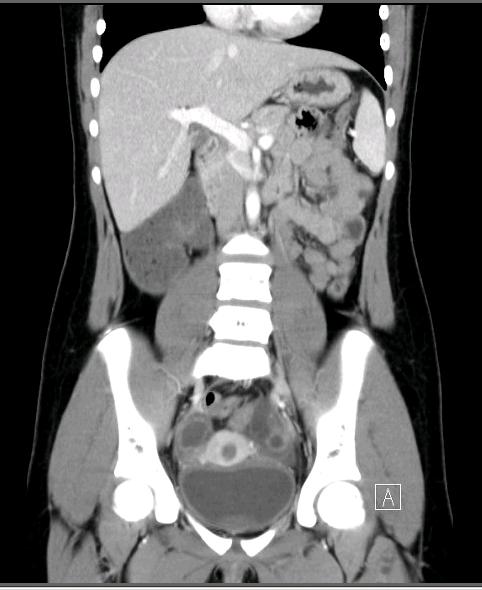

A tortuous tubular structure in the left adnexa raised suspicion for an isolated fallopian tube torsion (Figure 1). Results of an abdominal pelvic computed tomography scan confirmed a diagnosis of left fallopian tube torsion (Figure 2). The abnormal tubular structure was again visualized in the left adnexal region. The tubular diameter measured almost 2 cm. There was free fluid in the pelvis that was seen physiologically.